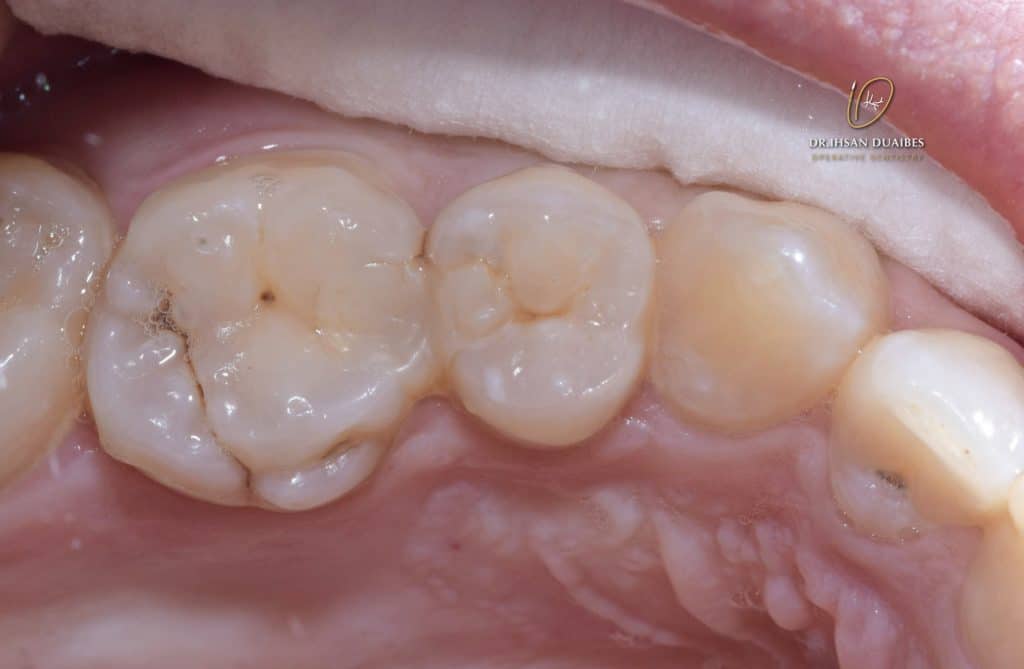

Finger restoration on 26 and 25

No symptoms

Suffering from food jams